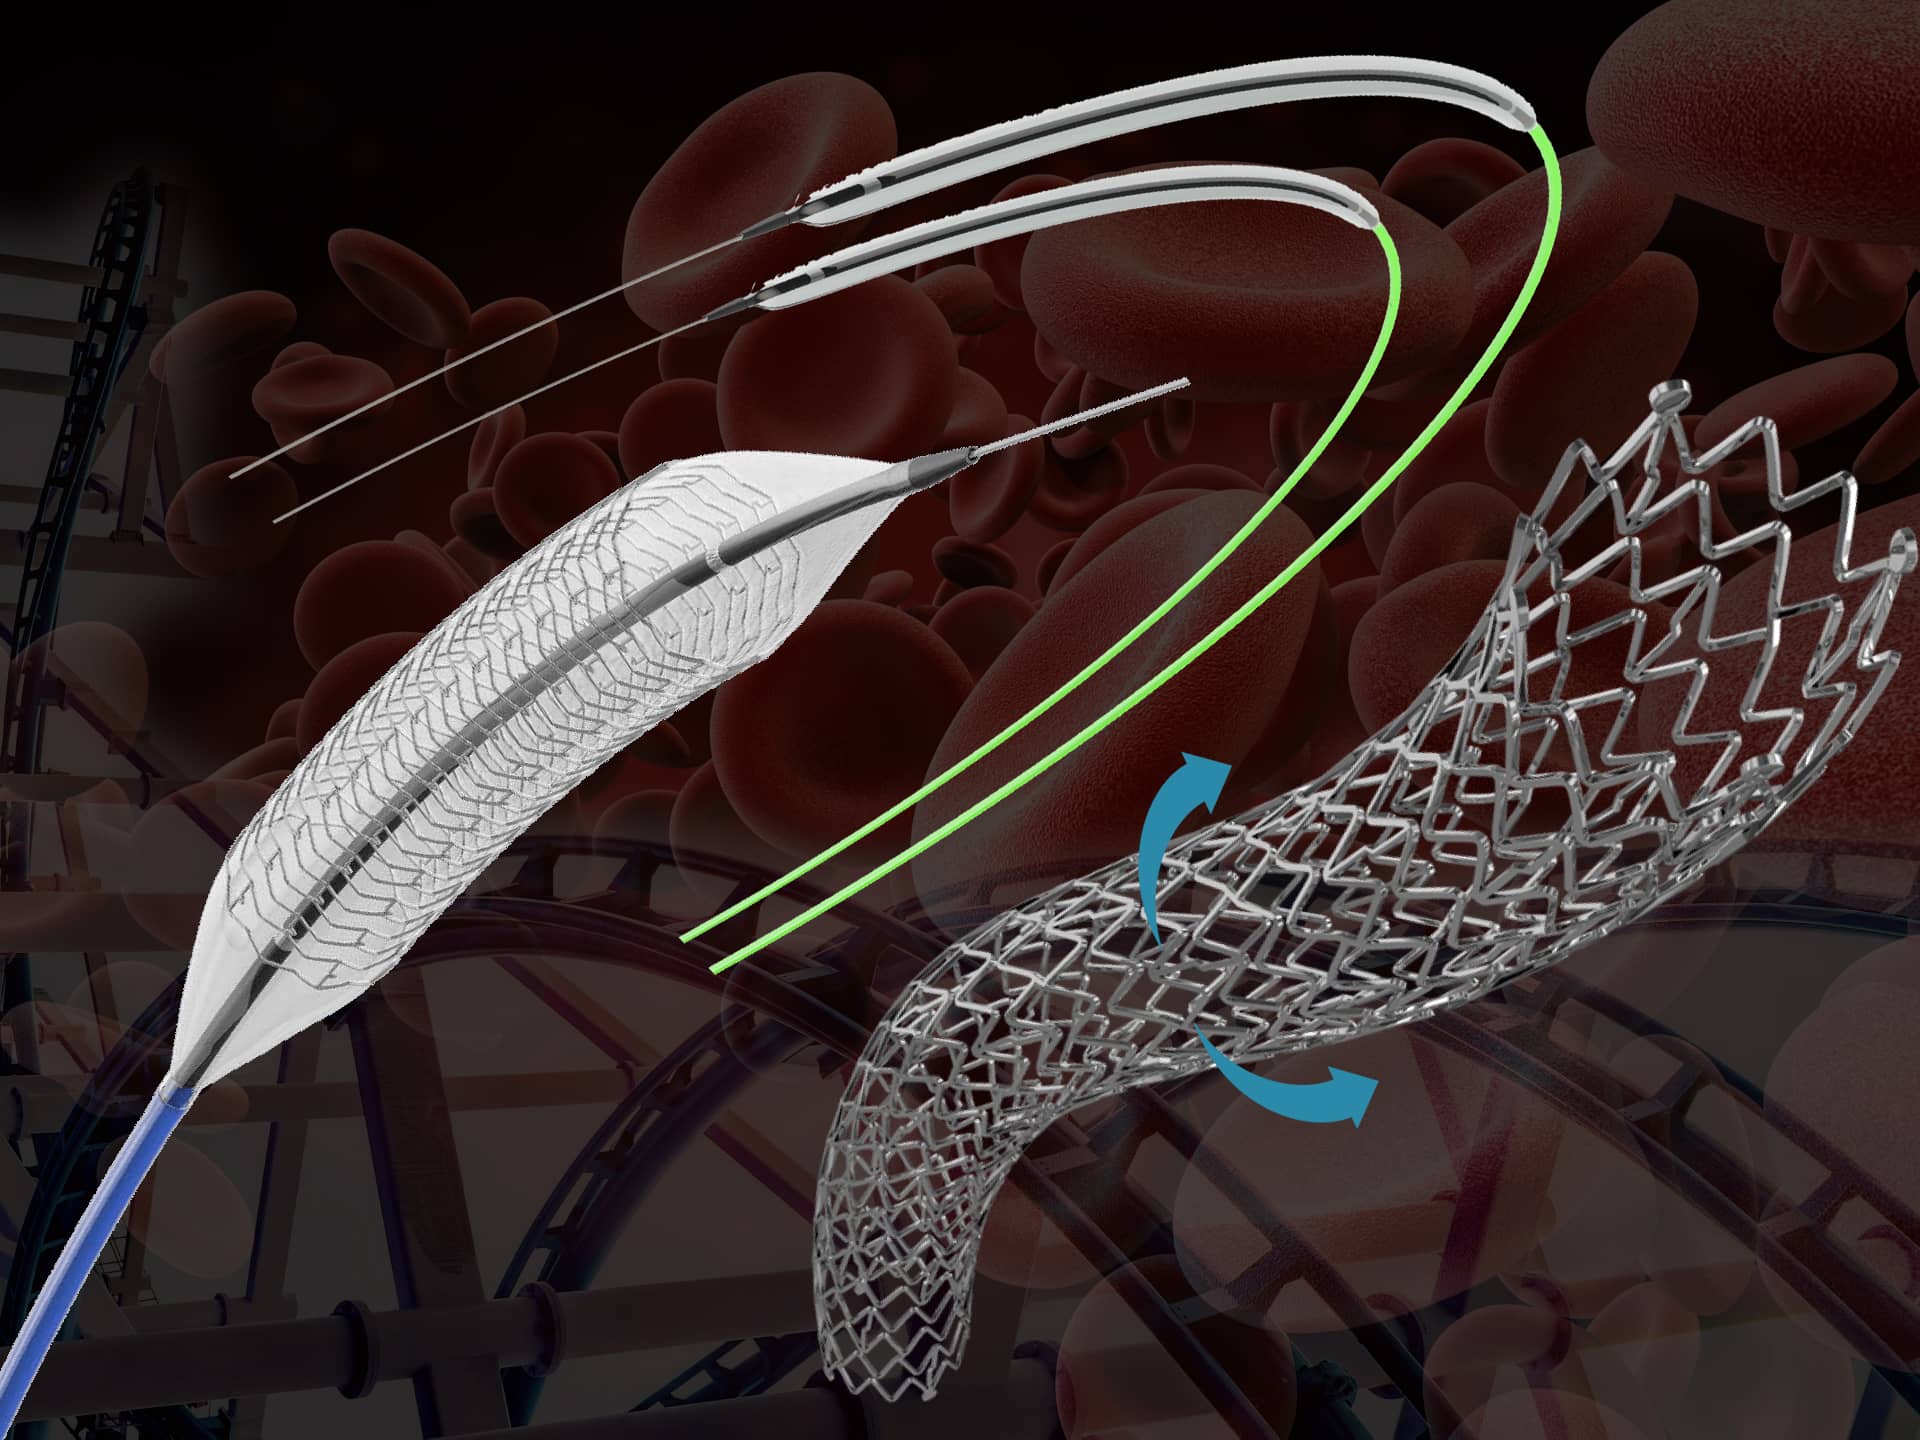

Thrombosis is a serious condition where one or more blood clots form in your blood vessels or heart. When this happens, the clot can block blood flow where it formed, or it can break loose and travel elsewhere in your body. If a moving clot gets stuck in a critical area, it can cause life-threatening conditions like stroke and heart attack.